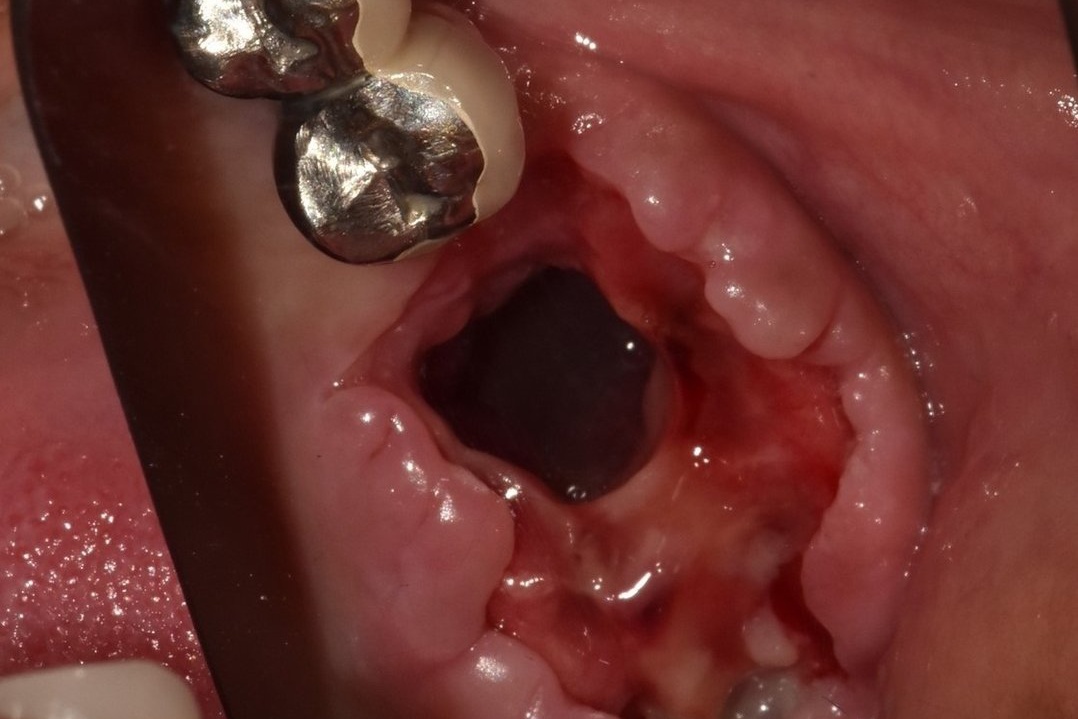

상악동 누공은 입과 코가 개통되는 증상입니다.

- 상악동 거상술이나 염증이 심한 상악의 치아를 발치하는 경우 속발성으로 상악동 누공이라는 증상이 생길수 있습니다.

- 이 증상은 구강에서 생긴 구멍이 상악동에 연결되어 막히지 않는 질환으로 물을 마시면 코로 물이 흐르는 등의 일상 생활에 상당한 불편을 초래합니다.

- 이러한 누공을 폐쇄시키는 수술은 상당한 전문적 기술과 경험을 필요로 하며 구강외과의 전문 분야로서 전문의의 진료 및 적절한 폐쇄 수술이 필요합니다.

- 누공이 적절하게 폐쇄된 이후에는 치아의 수복을 위해 치조골 이식과 임플란트 수술이 동반되는 경우가 많습니다.

상악동 누공 폐쇄 케이스

안녕하세요. 내인생치과 신창훈입니다. 이번에 소개해 드릴 환자분은 발치후 상악동이 천공 되어서 입안의 물이 코로 들어가고 코로 바람이 새는 증상이 있어서 발치한 치과에서 비흡수성 차폐막으로 막은 상태로 오셨습니다. 저희 치과에 오신 거는 발치한 날로부터 약 3주가 지난 상태로 오셨는데 발치한 치과에서는 한달이 안 되었기 때문에 더 기다려 볼 것을 권유 받…